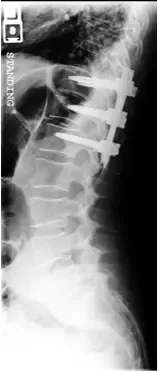

The fracture was stabilized by Minimal Invasive spine surgery with percutaneous pedicle screws in T11, 12 and L1 and rod fixation.

Patient tolerated the procedure well. She was pain free after the surgery and discharged home after 1 day. She was able to return to her usual activities in about 8 weeks.